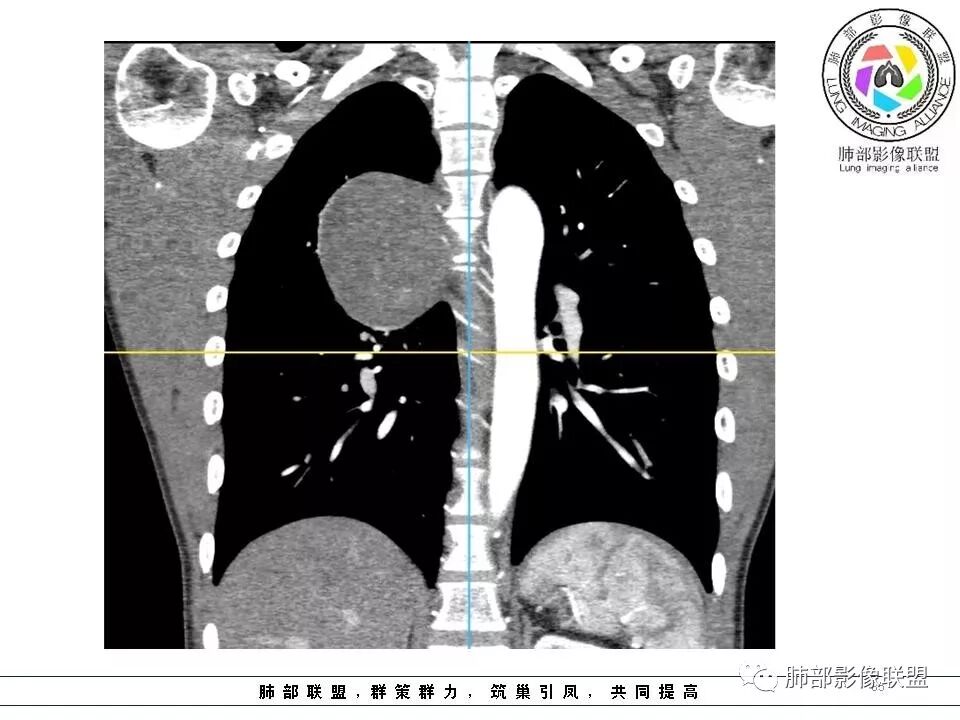

右肺占位,跨越上叶后段、下叶背,边缘光滑,瘤肺界面清,见肺压缩缘(线样不张`强化),见胸膜尾征,胸膜下脂肪未见明显增厚,肋骨丶脊柱未见侵袭及受压,渐进性丶地图样强化,冠状位似见体循环供血

右侧后纵膈肿块,有胸膜尾征,周围肺组织及支气管被推压,定位肺外,脏层胸膜来源,血供来自肺动脉或者支气管动脉,增强后持续渐进强化,蛇纹征,考虑SFT,鉴别鞘瘤。

右上肺野脊柱旁软组织肿块,边缘光滑整齐,肺组织及气管右肺上叶支气管受压前移,外移,边缘可见胸膜尾征,病灶内密度不均,增强后渐进性持续强化,其内可见明显蛇纹血管征,首先考虑肺外来源,sft.可能性大

边缘光滑,宽基底与胸壁相连,跨叶裂,叶裂稍前推,血管、支气管前移。

浅分叶

外上侧少量胸水

肋间动脉供血,强化尚均匀,逐步强化

1.右上胸内脊柱旁类圆形肿块,质地似乎比较坚实,密度稍显不均,但未显示明确的坏死。

如此密度形态的病灶位于肺边缘首先应当想到孤立性纤维瘤,可相邻胸膜未见明显的异常强化和胸膜方向延伸。

2.肋间动脉病供血也提示肿块来自后纵隔?